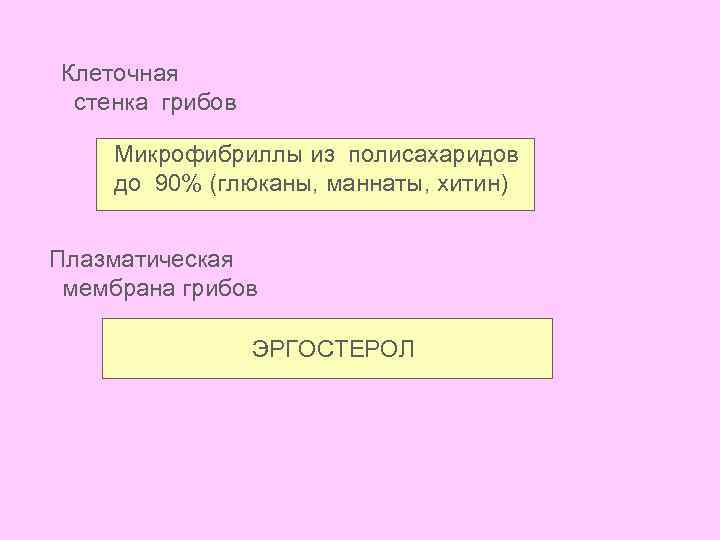

Клеточная стенка грибов Микрофибриллы из полисахаридов до 90% (глюканы, маннаты, хитин) Плазматическая мембрана грибов ЭРГОСТЕРОЛ